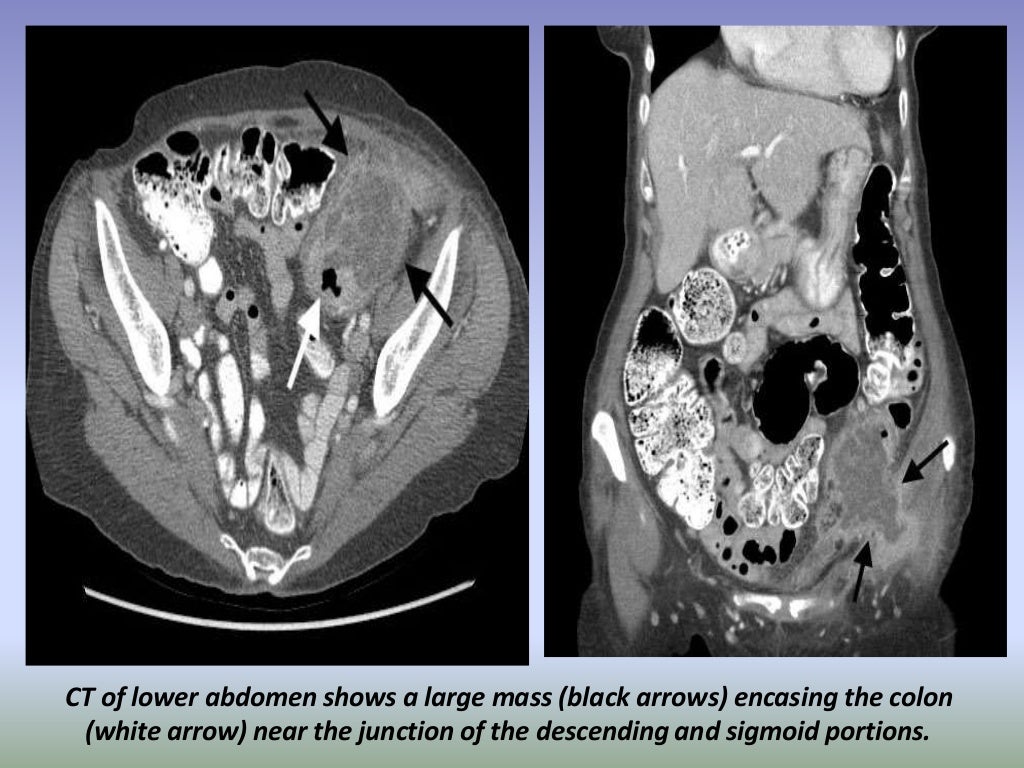

Presentation1.pptx, radiological imaging of large bowel diseases